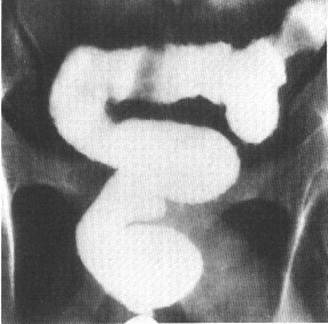

Fig. 49 – Diverticuli colici (magini aditionale opace, rotunde sau ovalare, net conturate, de dimensiuni variabile, sesile sau pediculate)

- diverticuli de pulsiune – apar ca imagini aditionale opace, rotunde sau ovalare, net conturate, de dimensiuni variabile, sesile sau pediculate, ce se evacueaza uneori cu dificultate (diverticulita).

- diverticuli de tractiune – realizeaza opacitati aditionale de forma triunghiulara cu baza pe lumen, neregulat conturate.